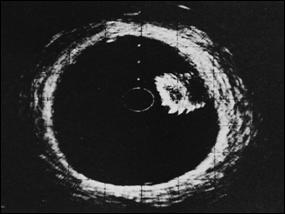

Figura 35. Aspect ecografic de tumora vezicala-transductor transuretral [dupa 132].

Daca in cazul tumorilor exofitice, diagnosticul de tumora prezenta in vezica nu este greu de pus, stadierea tumorii este practic imposibila ecografic, desi au fost incercari in acest sens.

Chiar folosind transductor transuretral, stadierea nu este de finete; se pot confunda usor tumorile T1 cu T2 si T2 cu T3 [251].